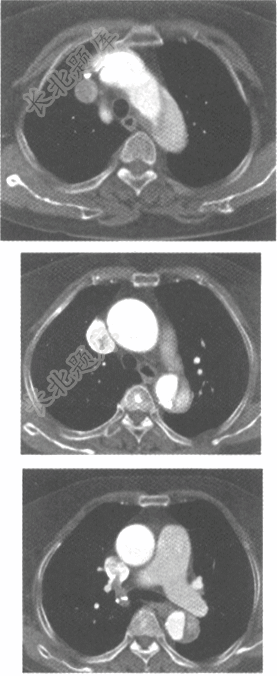

- 单项选择题男,67岁,突感胸腹部疼痛就诊。既往高血压病史。CT检查如下图,最可能的诊断是为

A、主动脉夹层(Stanford A型)

B、主动脉夹层(Stanford B型)

C、动脉硬化

D、大动脉炎

E、主动脉瘤